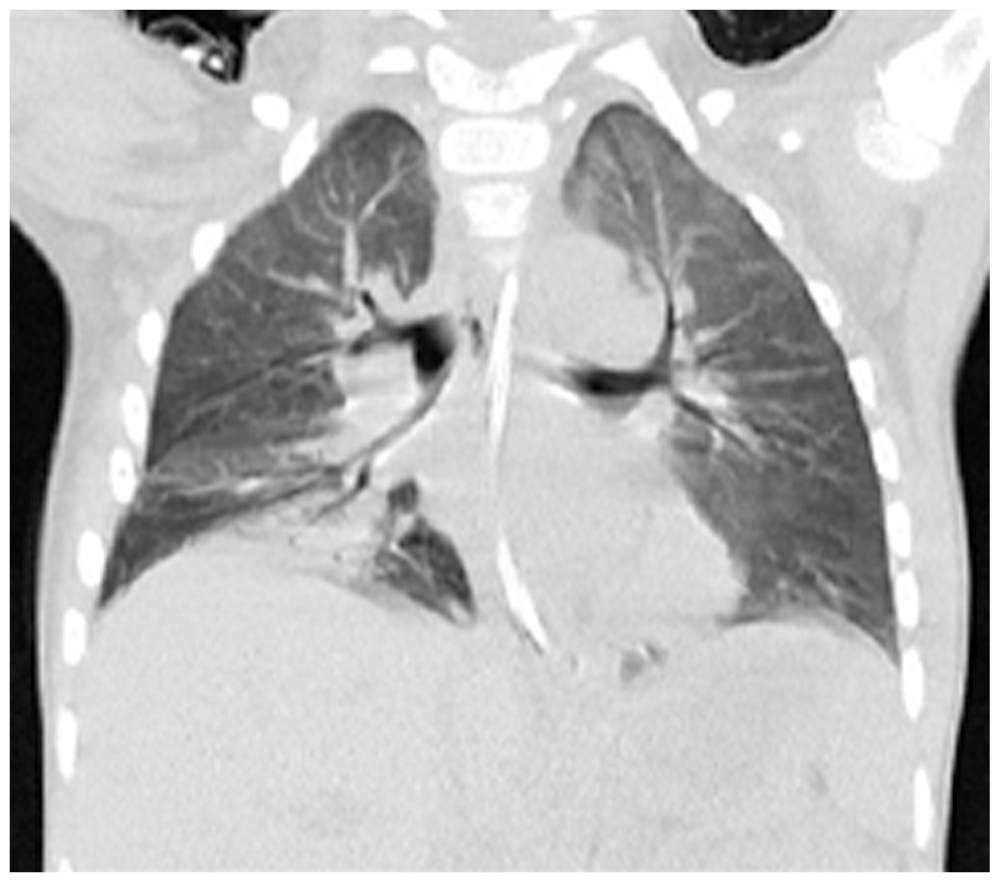

При поступлении выполнена спиральная компьютерная томография (СКТ) в режиме «Whole body». На основании клинико-инструментального обследования с учётом анамнестических данных и данных первичного стационара был сформулирован диагноз: «Тяжёлая сочетанная травма [оценка по шкале тяжести травмы (Injury Severity Score) 41 балл]; закрытая тяжёлая ЧМТ [по шкале оценки тяжести изолированных повреждений (Abbreviated Injury Scale, AIS) AIS-4]; ушиб головного мозга тяжёлой степени; перелом левой височной, теменной и затылочной костей; закрытая травма груди (AIS-4); множественные переломы рёбер (2–8) справа; ушиб левого лёгкого средней степени тяжести; разрыв правого лёгкого; большой напряженный пневмоторакс справа (AIS-4); закрытая травма живота (AIS-3); разрыв правой доли печени; гемоперитонеум; травматический шок 3 степени». Ребёнок был госпитализирован в отделение реанимации, где продолжена интенсивная терапия. Тяжесть состояния ребёнка была обусловлена тяжестью травматических повреждений с развитием множественной органной дисфункции в рамках синдрома взаимного отягощения. По плевральным дренажам сохранялось продувание воздуха, аускультативно определялось ослабление дыхания над всей поверхностью правого лёгкого. По данным СКТ при поступлении и рентгенографии органов грудной клетки, выполняемой ежедневно в палате отделения реанимации, сохранялось коллабирование правого лёгкого от ⅓ до ⅔ (рис. 1).

Рис. 1. Спиральная компьютерная томография при поступлении: коллабирование правого лёгкого с большим пневмотораксом.

Fig. 1. Spiral computed tomography at admission: collapse of the right lung with a large pneumothorax.